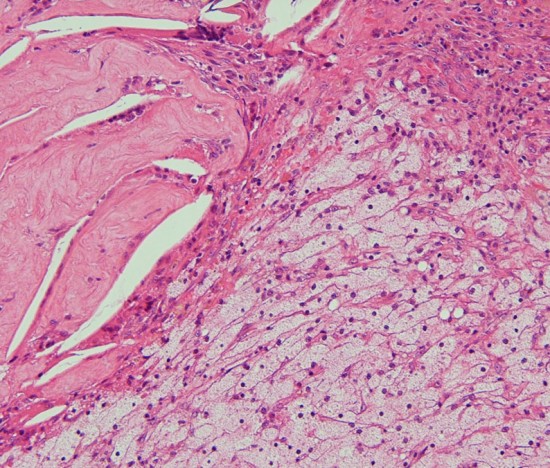

視床下部浸潤(よくあることで重要)

Adamantinomatous craniopharyngioma invading brain tissue. This type of hypothalamic invasion is frequently seen in the suprasellar/ intraventricular craniopharyngioma.

The border between tumor cells forming lateral palisading (center) and hypothalamic glial tissue (upper right) is not clear. There is no cleavage plane.